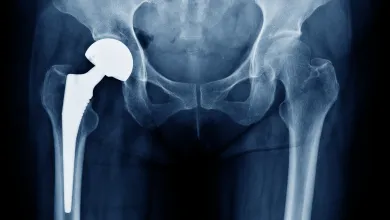

Returning to Elective Joint Replacement Surgery after a Pandemic

As the curve of COVID-19 cases starts to flatten, surgeons, patients, and facilities are [...]